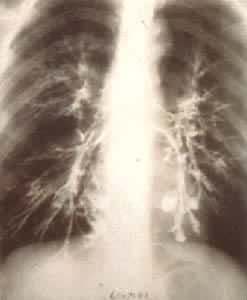

肺部疾病(一) 肺部疾病(二) 大叶肺炎 小叶肺炎 间质性肺炎 肺脓肿(正位) 肺脓肿(侧位) 支气管扩张 浸润性肺结核